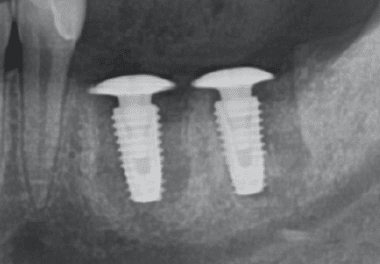

BIOARK, designed to provide underhead cuff space for bone and soft tissue healing, is an exceptional innovation for GBR (Guided Bone Regeneration) and all the intricate cases involving various augmentation procedures, presenting superb osteogenesis

Routine implant placement.

Checking the appropriate depth and then performing facile bone augmentation.(Place the fixture mount to prevent the bone material from falling into the implant fixture.)

Using BIOARK, then select appropriate length-1 mm below from marginal soft tissue. With enough endentulous space, BIOARK of usual size 1.5 larger than the fixture platform surface is used (If mesiodistal interference is to be seen, 1 size smaller BIOARK s

Removing the suture after 1 week. Switching to healing abutment after bone regeneration and soft tissue healing.